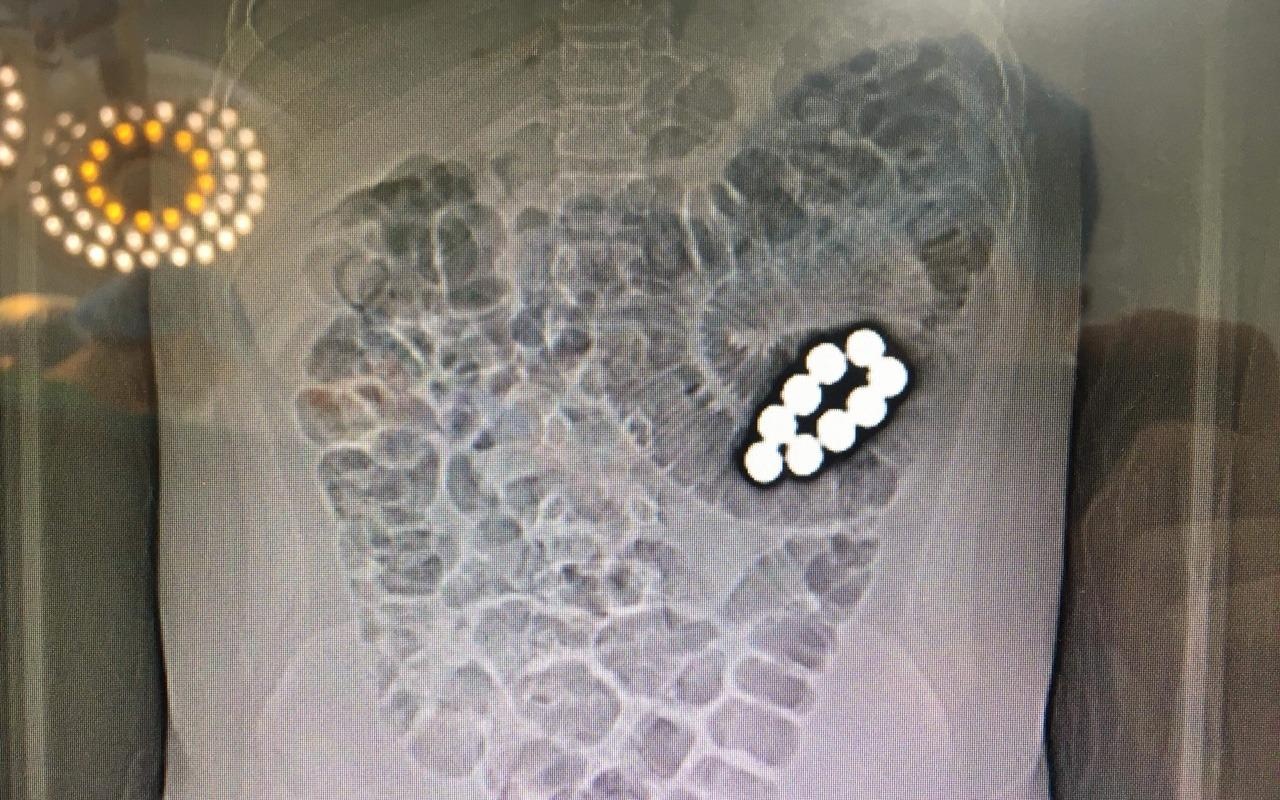

Vụ việc nam sinh lớp 5 trường Tiểu học An Bình B (Bình Dương) nghi bị ép nuốt 9 viên bi sắt, suýt tử vong, đã được báo cáo công an địa phương.